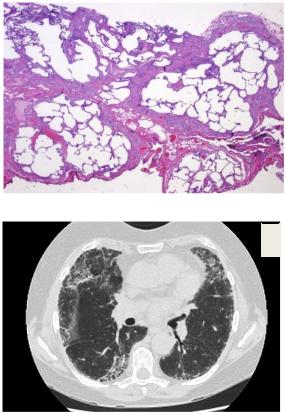

Гистологическая картина обычной

интерстициальной пневмонии (ОИП)

Рентгенологический паттерн ОИП